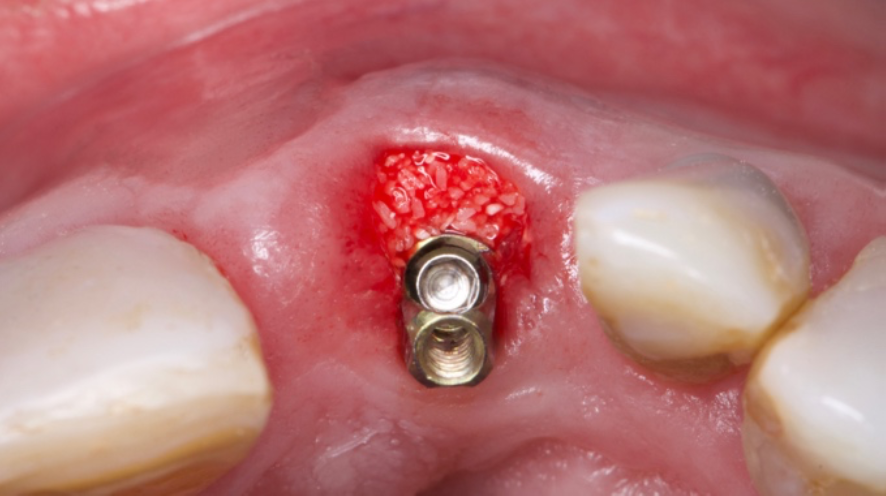

A colocação imediata bem-sucedida do implante requer consideração cuidadosa de vários fatores. A seleção do caso desempenha um papel crucial para determinar a adequação e colocação imediata do implante. Fatores como a presença de infecção ou inflamação no alvéolo de extração podem afetar o sucesso do procedimento. Uma curetagem completa e limpeza do alvéolo são necessárias para remover qualquer tecido infectado ou inflamado antes da colocação do implante. A qualidade e a quantidade adequadas de osso também são considerações importantes para a colocação de implantes imediatos bem-sucedidos.

O planejamento no tratamento de implante imediato deve incluir uma avaliaçãocompleta do alvéolo de extração, osso circundante e tecidos moles. Essa avaliação ajuda a determinar o tamanho, o tipo e a técnica de colocação do implante.